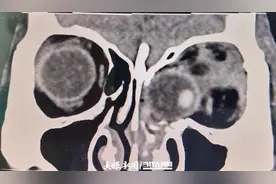

来源:天眼新闻 日前,贵州医科大学附属医院创伤科接诊了一位特殊的患者:50岁的黄女士(化名)因一脚踩空不慎从3楼坠落,导致全身多处疼痛及左眼视力丧失,被紧急送往该院救治。经检查,黄女士的伤情极为严重,左眼球脱位并嵌顿于鼻腔内,情况十分危急。

“患者眼球脱位,请眼科急会诊!”10月25日晚,贵州医科大学附属医院(以下简称“贵医附院”)眼科眼眶专科组组长杨夏接到紧急指令。10月25日21时许,黄女士因“高处坠伤致全身多处疼痛1+天”到贵州附院创伤科就诊。